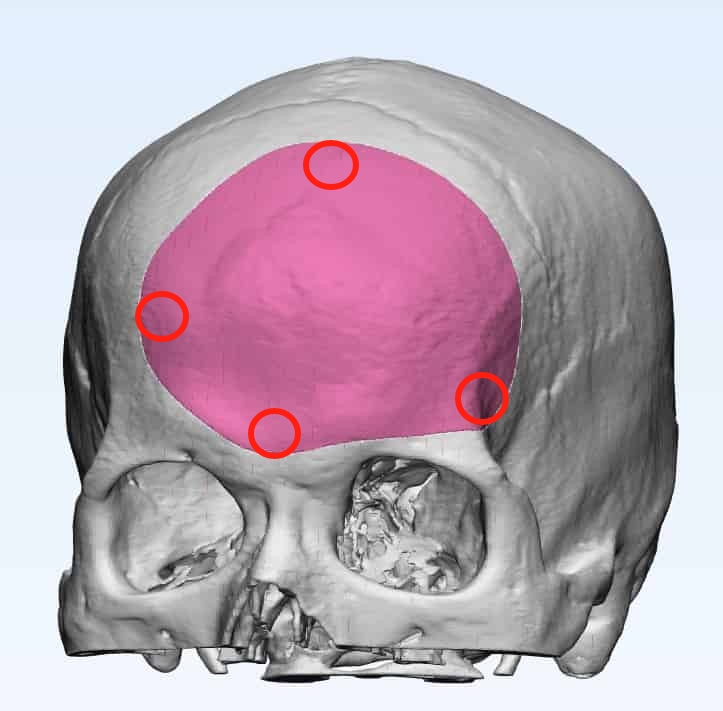

■ “導板”確定腫瘤體表投影,導航驗證,圍繞骨質增生后緣設計冠瓣切口(切口偏后相對美觀及切緣離開植入物表面);

■ 使用“導板”確定骨窗范圍,用記號筆標記。中線及兩側鉆孔4枚,沿標記內側2mm銑下骨瓣,暴露矢狀竇,注意矢狀竇旁蛛網膜顆粒出血,明膠海綿壓迫,必要時時抬高背板;